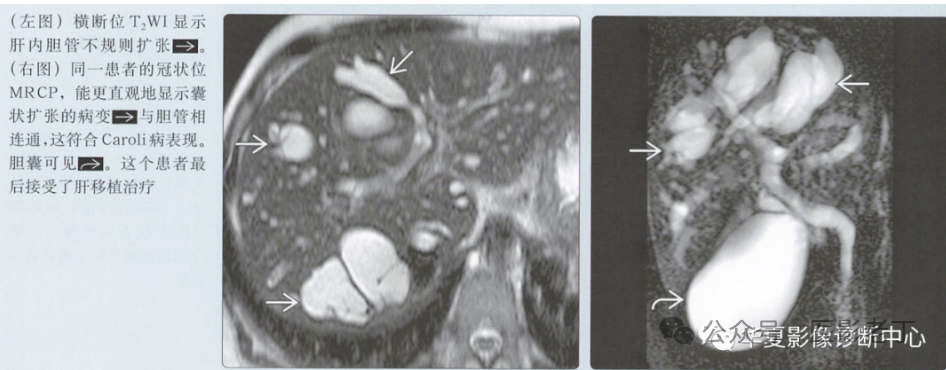

• 肝内胆管呈阶段性扩张;沿肝内胆管走向发布;与胆管树相通;

• 中心圆点征:增强CT上扩张的肝内胆管内可见小强化点(门静脉小分支);

2、MRCP、ERCP:

确诊方法,MRCP清楚显示与胆管树相通,显示”悬挂“征;